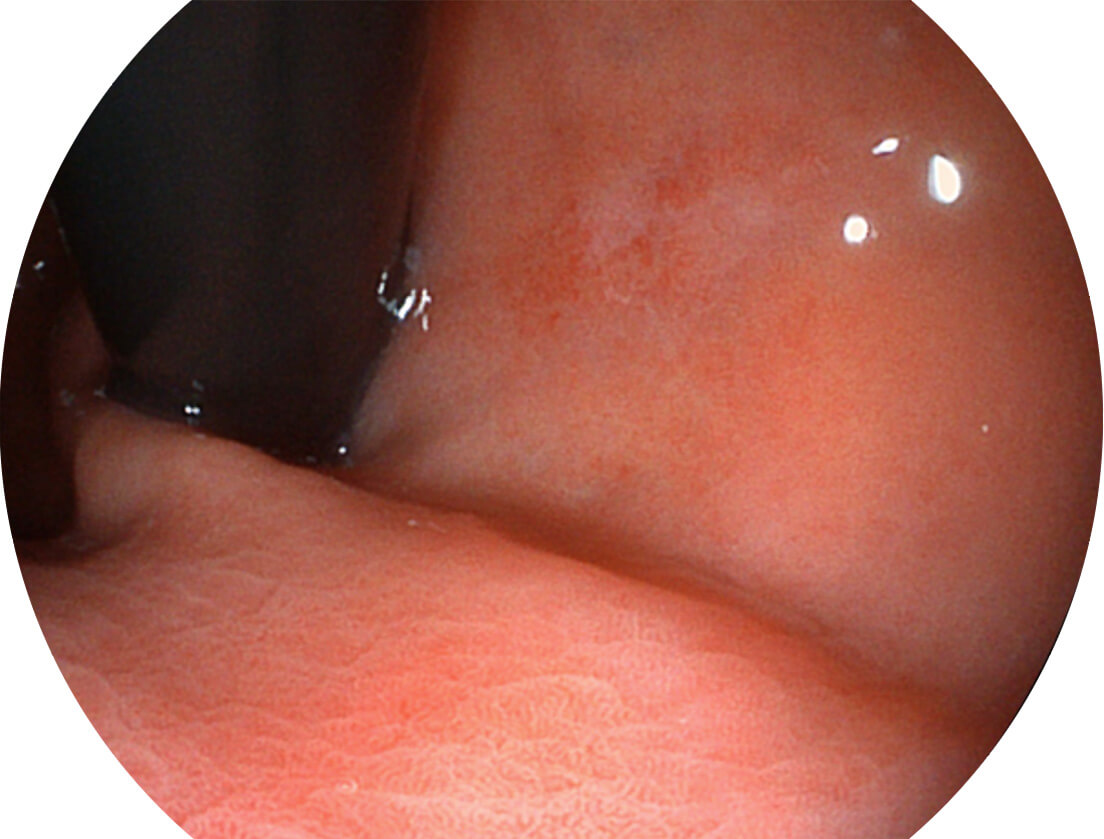

强调浅层黏膜结构的同时,保证照明亮度和提升浅层微血管与中层血管颜色对比度,病变边界更清晰。

• 白光图像 VIST图像